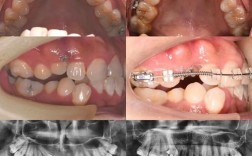

- 您处理过类似我这种错颌类型(如骨性、复杂拥挤、深覆颌等)的案例吗?能给我看看吗?(要求看真实的、与你情况相似的案例照片/视频,注意是治疗前后对比)

- 要求医生用模型、X光片(全景片、头颅侧位片)、口扫或照片等工具清晰地展示你的问题。

- 案例对比: 一定要看医生真实的、与你情况相似的矫正前后对比案例,这是评估医生能力和效果预期最直观的方式。